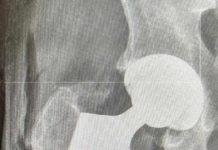

W Szpitalu Powiatowym im. PCK w Nisku przeprowadzono pionierski innowacyjny zabieg

W sobotę w Szpitalu Powiatowym im. Polskiego Czerwonego Krzyża w Nisku, zespół pod kierownictwem lekarza med. Tomasza Chmielewskiego, kierującego Oddziałem Ortopedycznym niżańskiego Szpitala, przeprowadził pierwszą w Polsce i Europie...